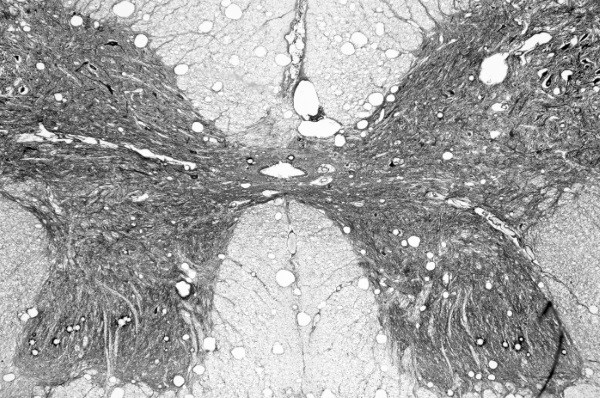

Передние и задние рога серого вещества спинного мозга окружены белым веществом.

Белое вещество

Белое вещество состоит из пучков миелиновых нервных волокон, которые образуют нервные пути, проходящие вверх и вниз по позвоночнику и соединяющие мозг в обоих направлениях. Восходящие нервные пути направляют сенсорные импульсы в мозг, а нисходящие отправляют двигательные команды в ПНС.